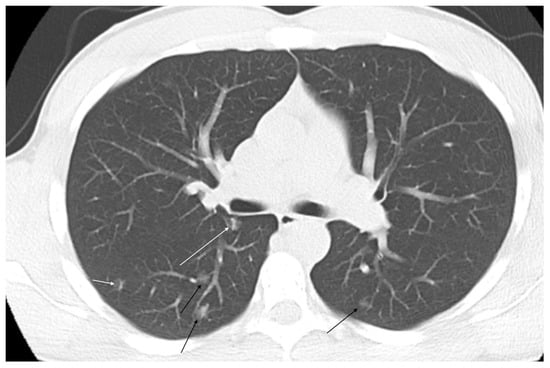

3.2. Computed Tomography (CT)